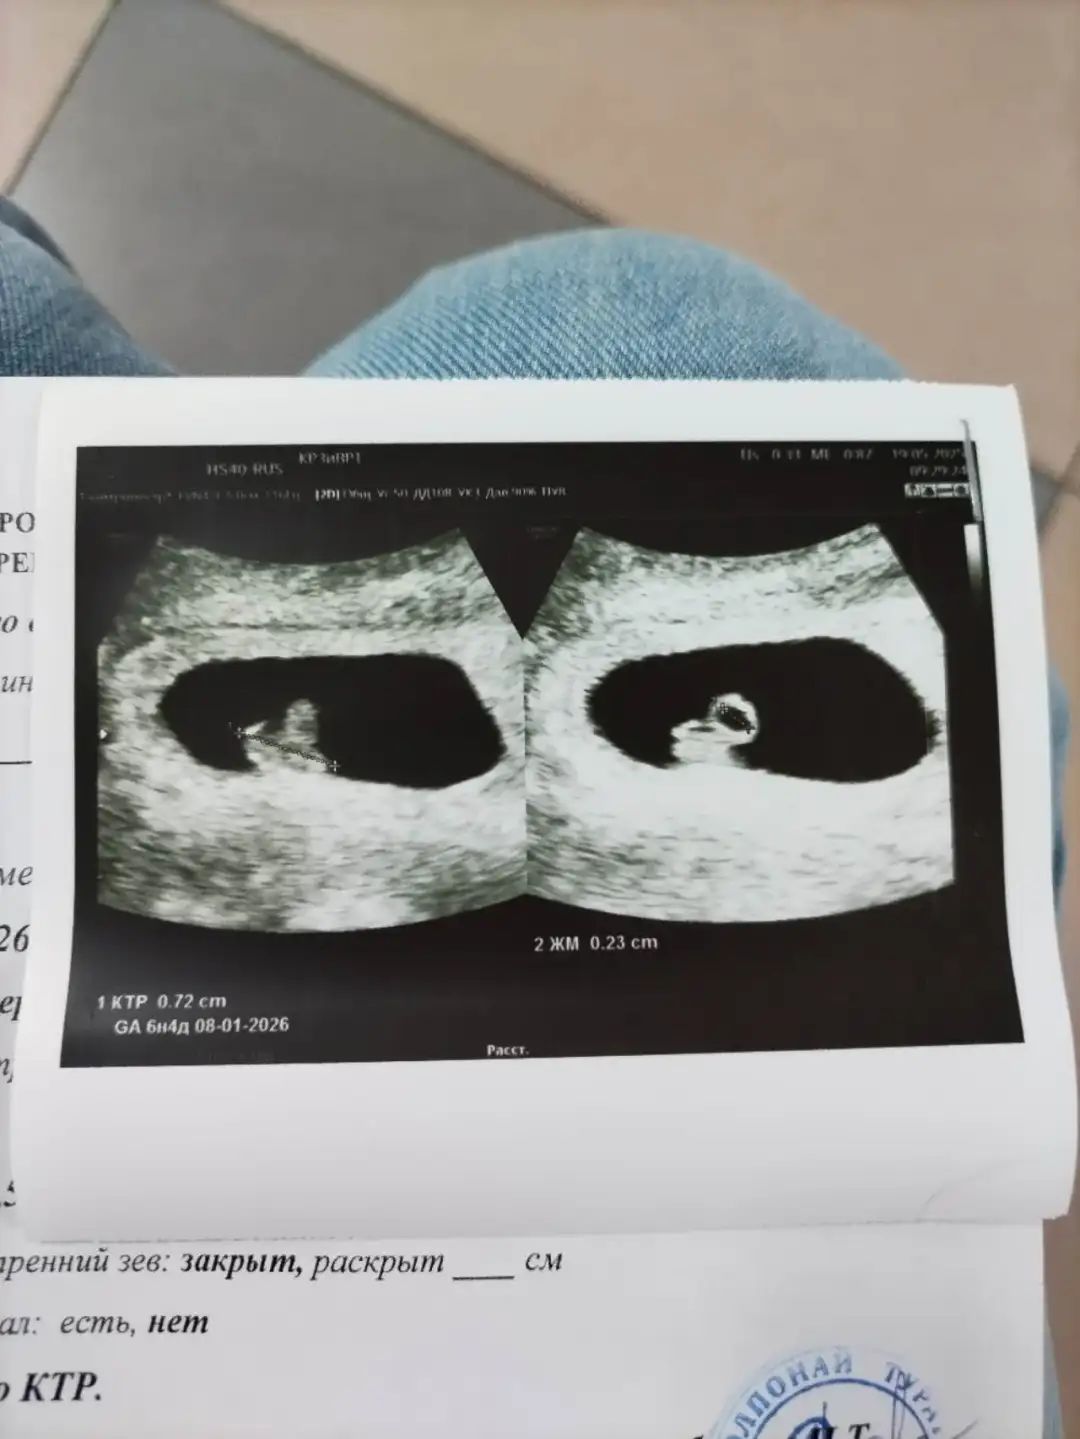

移植后还需要通过定期的血液检查和B超检查,监测胚胎着床和发育情况。